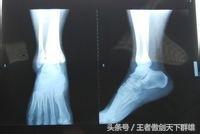

第一步,如果崴到脚,脚踝立刻就肿胀,而且很痛,建议首先到医院拍张片子看一下有没有伤到骨头。